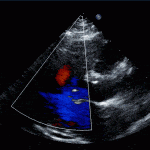

- Partial AV Canal Defect –> aka Primum ASD

- Complete AV Canal Defect

- ASD above the valve

- VSD below the valve

- Instead of 2 valves –> One large AV valve